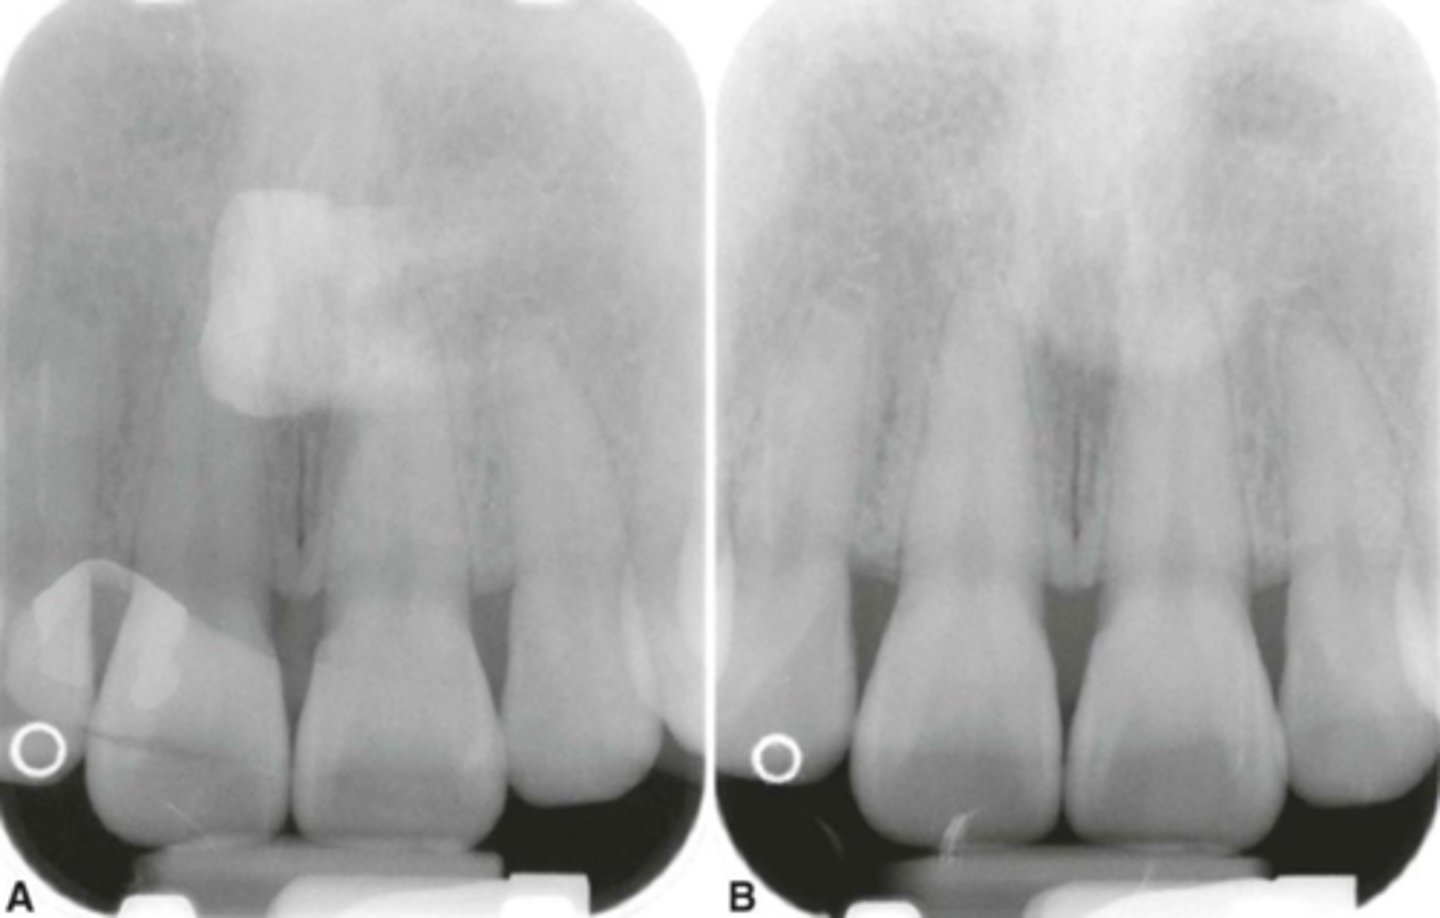

Cone-Cut with Beam Alignment Device

-A clear unexposed area is seen.

-PID was not properly aligned with the PA beam alignment device and the beam did not expose the entire receptor, resulting in a clear unexposed area resembling the outline of the PID is seen.

-To avoid make certain that the PID and the aiming ring are aligned.

Cone-Cut without Beam Alignment Device correction

Make certain that the x-ray beam is centered over the receptor and that the entire receptor is covered by the diameter of PID.